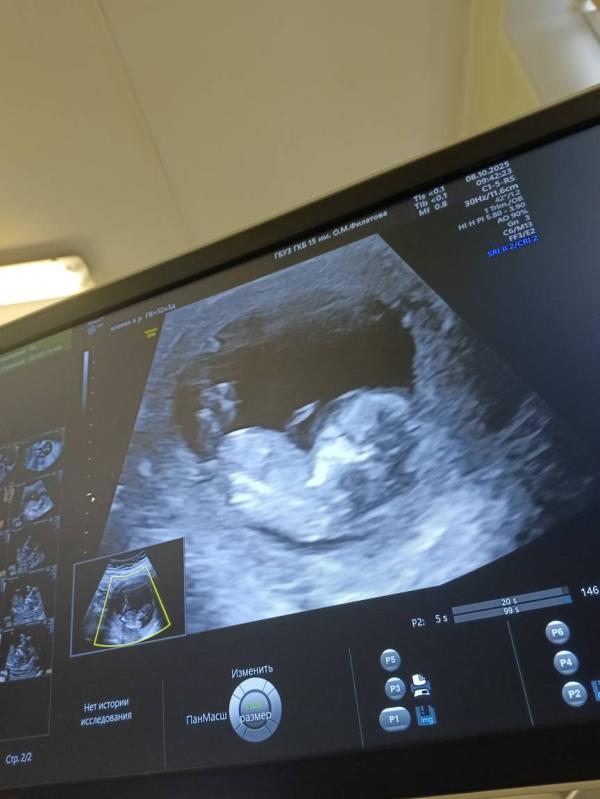

Первый скрининг 12 недель: результаты УЗИ и ЧСС 165

Прошла первый скрининг ✅

По УЗИ все хорошо, срок 12 недель 5 дней. ЧСС 165 ударов в минуту ❤️ Долго не могла разбудить, после шоколадки минут через 20 только проснулся😁

Мама тебя ждёт, котёночек 🥰